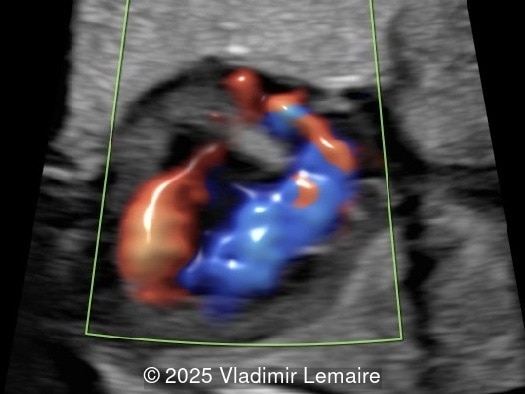

Four-chamber view with color Doppler. Blood enters the right ventricle across the VSD in late diastole and systole.

Image 3 Four-chamber view with color Doppler. Blood enters the right ventricle across the VSD in late diastole and systole.

Color Doppler confirms the diagnosis on grayscale ultrasound, as it demonstrates the lack of blood flow across the tricuspid valve and a patent mitral valve. Due to increased blood flow across the mitral valve, aliasing is typically noted on color Doppler. Mitral valve regurgitation has been associated with a poor outcome. The right ventricular cavity is filled in late diastole from the left ventricle, through the ventricular septal defect. Left-to-right shunting across the ventricular septal defect can be seen on color Doppler. Color Doppler is helpful in the evaluation of flow across the great arteries. Flow across the pulmonary artery is generally antegrade. Pulmonary stenosis should be suspected when the vessel is diminutive in size rather than the demonstration of turbulent flow on color Doppler, which is typically absent in these cases.